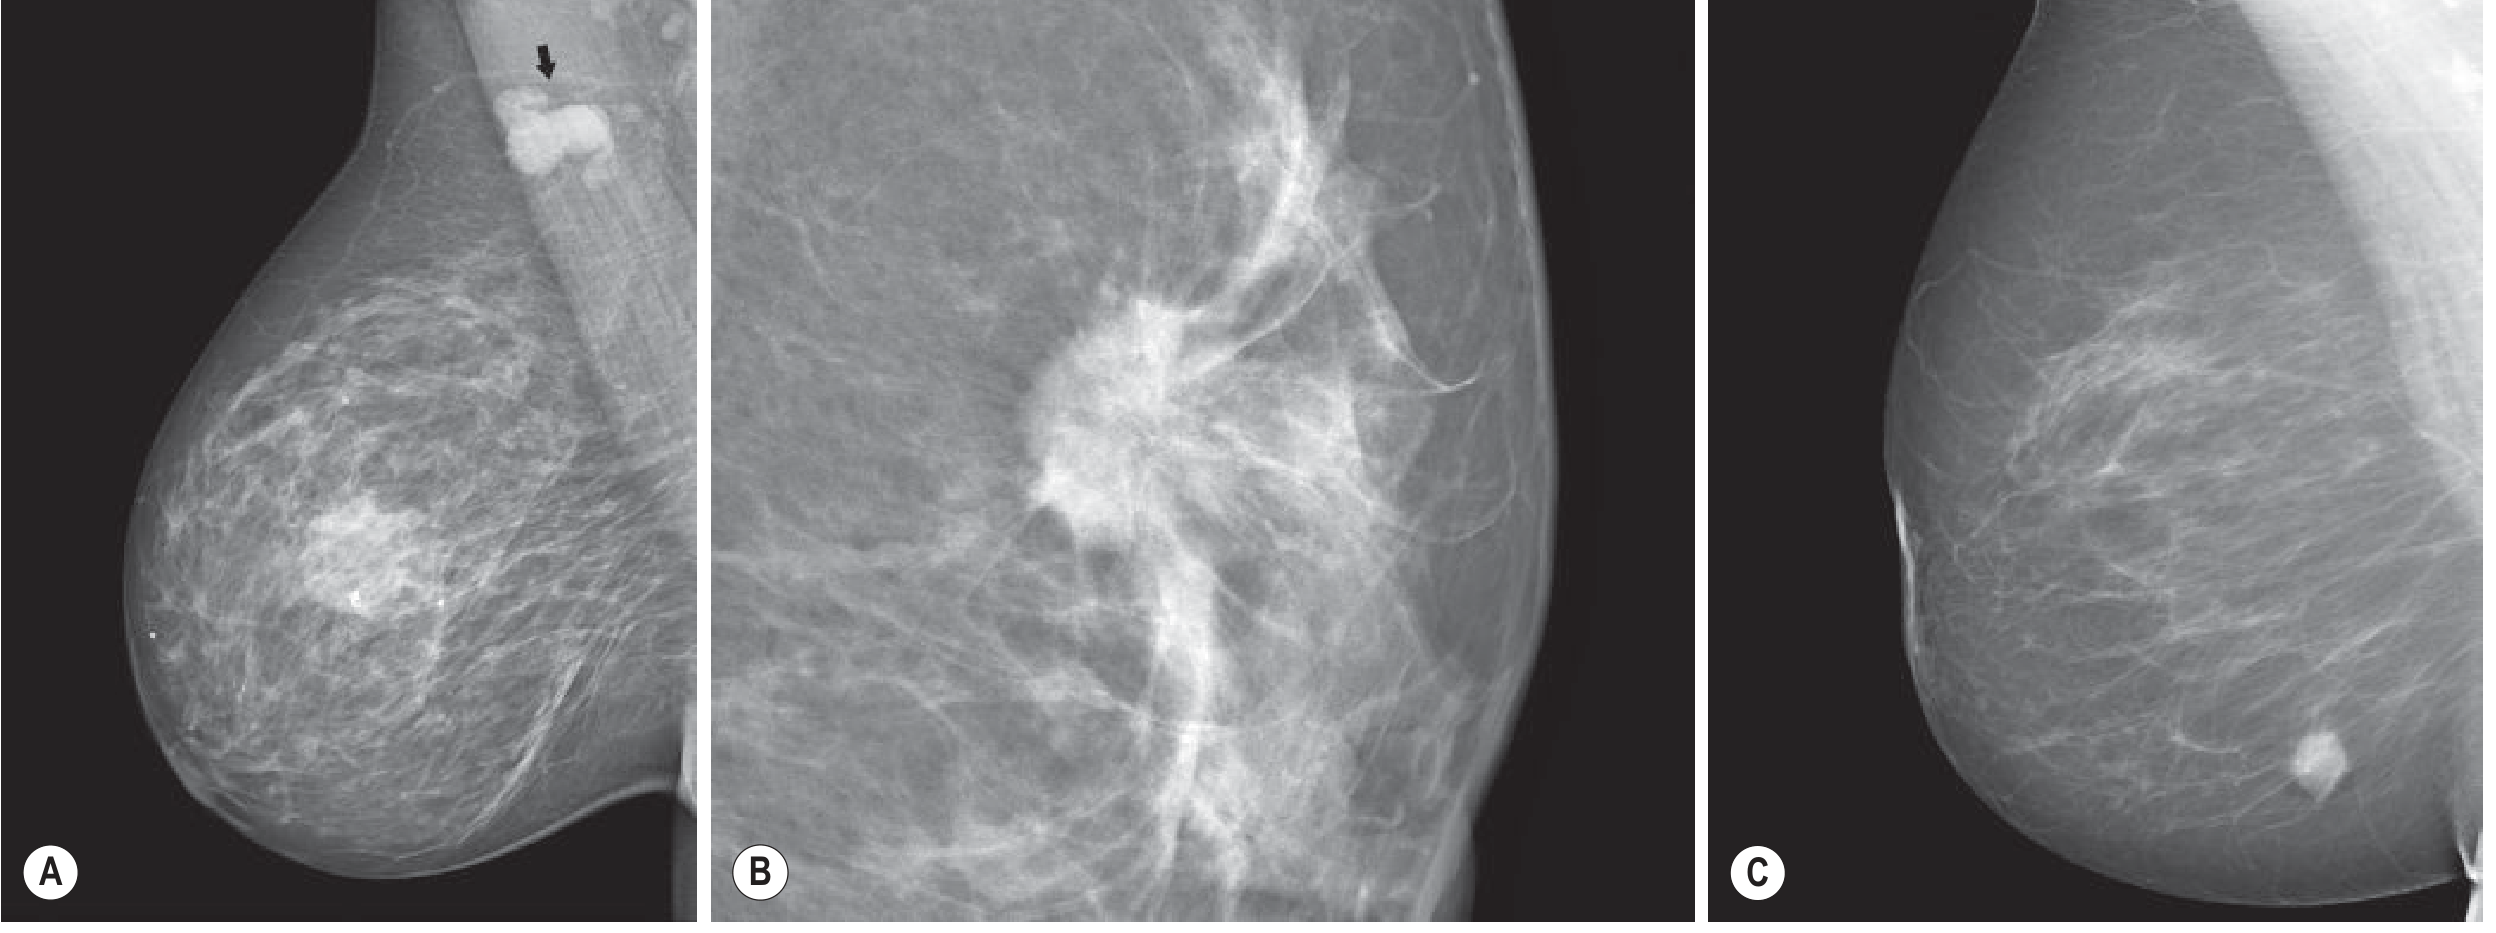

Mammographic appearances of invasive carcinoma — (A) ill-defined mass with enlarged axillary nodes, (B) classic spiculate mass, (C) well-defined high-grade tumour

Mammographic appearances of invasive carcinoma. (A) Ill-defined central mass with microcalcifications and enlarged axillary nodes. (B) Classic spiculate mass — ductal NST tumour. (C) Well-defined appearance seen in some high-grade tumours. — Grainger & Allison's Diagnostic Radiology